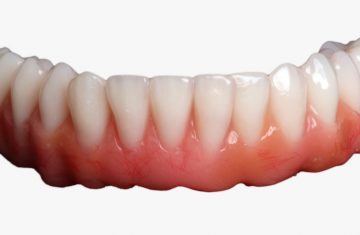

Cirurgia Guiada por Dr. João Marcelo Arcoverde

Adepto à filosofia de trabalho de que menos é mais, Dr. João Marcelo Arcoverde se tornou pioneiro no Brasil ao unir a técnica que permite repor dentes perdidos sem a necessidade de cortes e uso de bisturi convencional que diminuem drasticamente a necessidade de enxertos ósseos.

A Cirurgia Guiada é uma técnica inovadora, cujo implante dentário é feito sem cortes e pontos, portanto gerando maior conforto ao paciente, seja na reposição de um dente, de vários ou de todos.